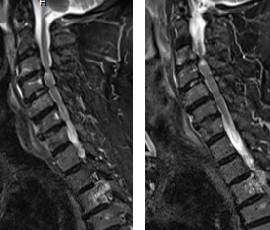

Myélopathie Cervicale